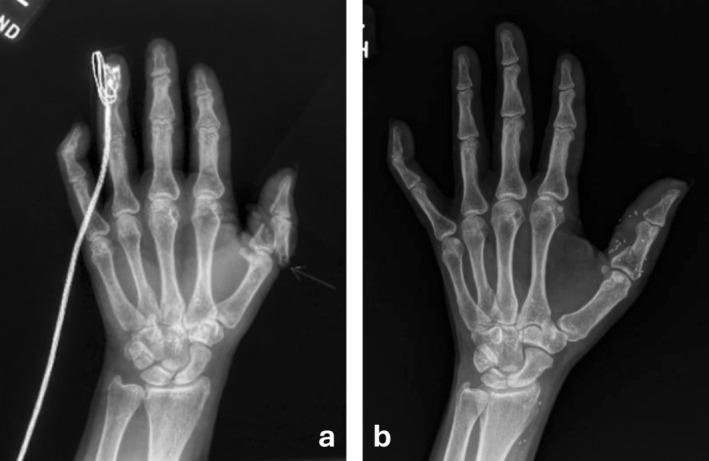

Use of Arterialized Venous Flaps to Preserve Full Digital Length in Revascularization of Partially Amputated Digits: Two Cases.

This case series illustrates the successful use of arterialized venous flaps (AVFs) in digital revascularization. AVFs facilitated tension-free vascular anastomosis and provided soft tissue coverage, allowing preservation of digital length while restoring function. Our findings support the expanding role of AVFs in hand trauma reconstruction and challenge the conventional necessity of bone shortening.

本病例系列说明了动脉化静脉皮瓣(AVF)在手指血管重建中的成功应用。AVF有助于无张力血管吻合并提供软组织覆盖,在恢复功能的同时可保留手指长度。我们的研究结果支持AVF在手部创伤重建中日益重要的作用,并对传统的骨缩短必要性提出了挑战。